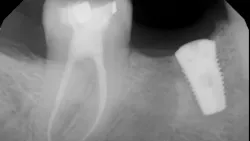

If definitive crown placement is delayed and the patient has excessive forces on the tooth or suffers from direct trauma, the tooth can fracture. In many cases, a decision must be made upon full bone healing versus the likelihood of crown fracture (figure 3–6). In addition, most studies show that full-coverage crowns are a main factor in determining long-term success of root canal therapy, with successes ranging from 92% for teeth receiving crowns compared to 35% for those not receiving crowns after a one- to five-year follow-up.2 In another study on molar teeth five years after root canal therapy, teeth that had crowns placed had a success rate of 78% versus 36% without crown coverage.3